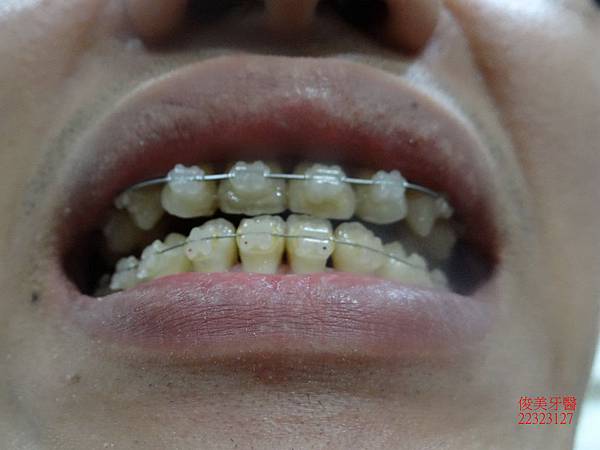

原始狀況~~

咬合狀況。

上排牙明顯被下排牙齒限制住。